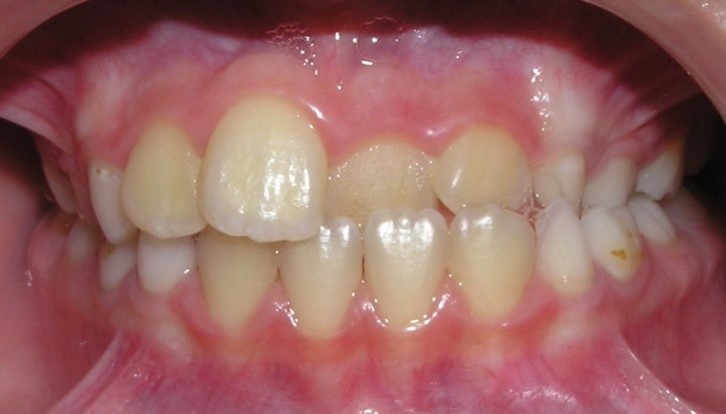

(one or both) - 61.35%. In 57% of children, there are erased areas on the

incisal and vestibular surfaces of palatal-displaced teeth as a result of the

functional action of antagonist teeth. With a slight overlap, abrasion of the

cutting edge and shortening of the abnormally located tooth are observed. In the

palatal location of the upper jaw incisors, flattening of the frontal area of

the upper jaw and lengthening of the frontal area of the lower jaw are

determined. In this case, exposure of the necks of the lower frontal teeth,

violation of their stability and inflammation of the gums may be observed, and

the clinic of catarrhal or atrophic gingivitis develops as a result of

functional trauma.